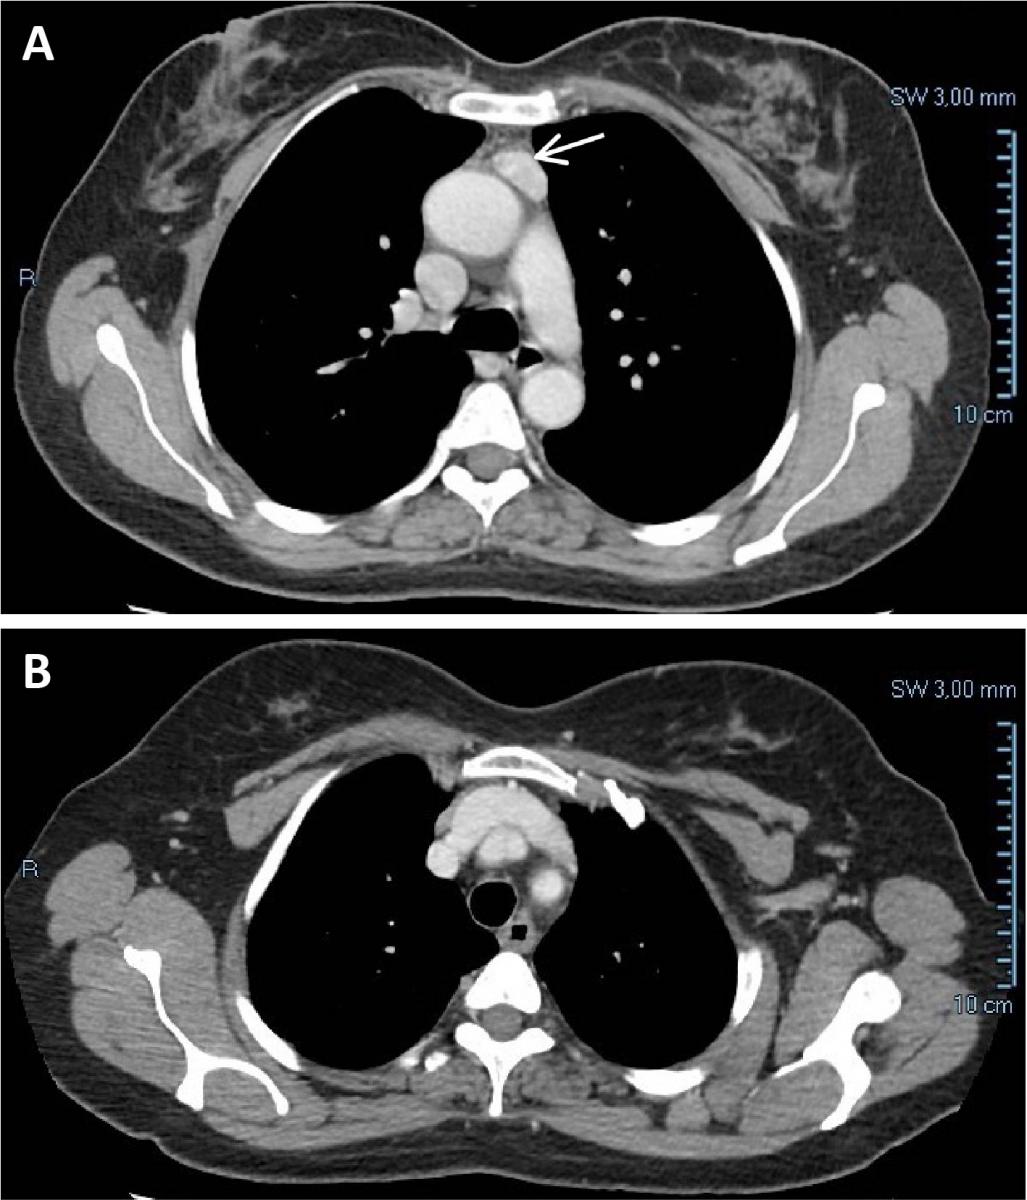

Figure 1. (A) Chest CT showing a tumor measuring 24 x 12 mm in the anterior mediastinum, suggestive of a small thymoma. The tumor showed a high contrast enhancement. There is a clear plane between the mass and the aorta and no compression of any mediastinal structures. (B) No connection with the cervical thyroid was observed. In retrospect, this is one of the features of mediastinal ectopic thyroid.

A 58-year-old woman sought medical treatment because of abdominal pain. Previously, she had been diagnosed with colonic diverticular disease. At the emergency department, an abdominal computed tomography (CT) was performed and no abdominal abnormality was seen. A 6 mm pulmonary nodule was detected in the left inferior lobe and a follow-up chest CT revealed an anterior mediastinum density below the level of the aortic arch, measuring 24 x 12 mm and showing high contrast enhancement (Figure 1). Lymphadenopathy, thymoma, ectopic thyroid, and parathyroid adenoma were the diagnostic hypotheses in the radiology department.